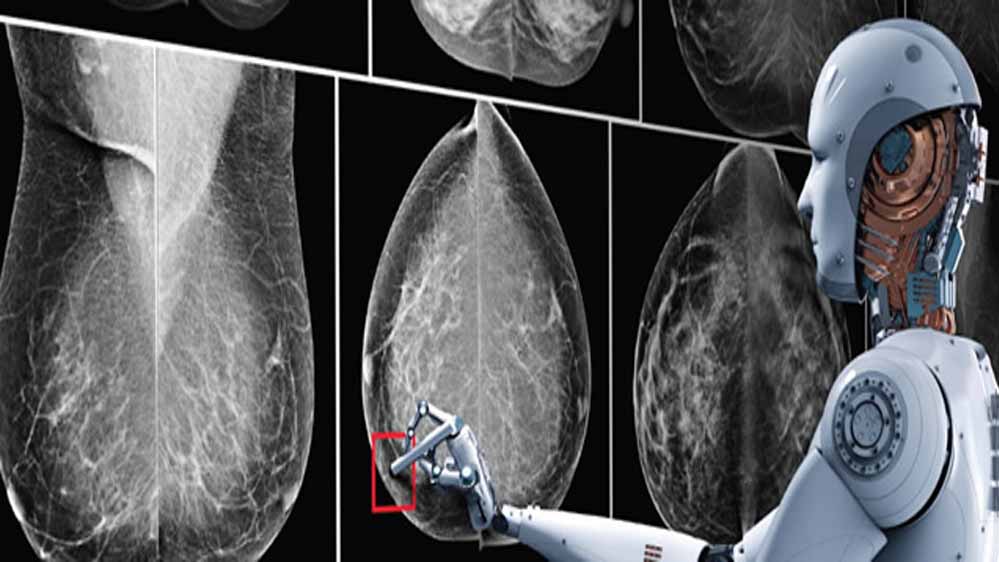

AI से डिटेक्ट करेगा ब्रेस्ट कैंसर

हाल ही में अमेरिका की Duke University के रिसर्चर ने एक New AI डेवलप किया है। इसके रिसर्चर ने दावा किया है कि, AI ब्रेस्ट कैंसर को उसके डेवलप होने से लगभग पांच साल पहले ही डिटेक्ट कर सकता है। अब आनंद महिंद्रा ने साइंस न्यूज नाम के हैंडल पर की गई पोस्ट को रिपोस्ट किया है। उन्होंने इस पर लिखा है कि यह बहुत काम का साबित हो सकता है।

कैंसर का पता लगाने के लिए फिलहाल Biopsies, Microscopic Histological एग्जामिनेशन मेथड का इस्तेमाल किया जाता है। इसके अलावा इमेजिंग टेक्नोलॉजी जैसे MRI, CT स्कैन और PET स्कैन हैं। अब रिसर्चर्स ने दावा किया है कि AI की मदद से एक्यूरेसी के साथ कैंसर की रिपोर्ट दे सकता है।

हाल ही में अमेरिका बेस्ड Duke University के रिसर्चर ने एक New AI डेवलप किया है. यह AI मॉडल कैंसर डेवलप होने से करीब 5 साल पहले कैंसर को बता देगा. ये दावा रिसर्चर ने किया है.

कैंसर का पता लगाने के लिए, जो ट्रेडिशनल तरीका है, वो Biopsies, Microscopic Histological एग्जामिनेशन है. इसके अलावा इमेजिंग टेक्नोलॉजी जैसे MRI, CT और PET Scans हैं. वहीं, AI सिर्फ मेडिकल इमेज को एनालाइज करके ज्यादा बेहतर एक्युरेसी के साथ कैंसर की रिपोर्ट दे सकता है, जो दावा रिसर्चर ने किया है.